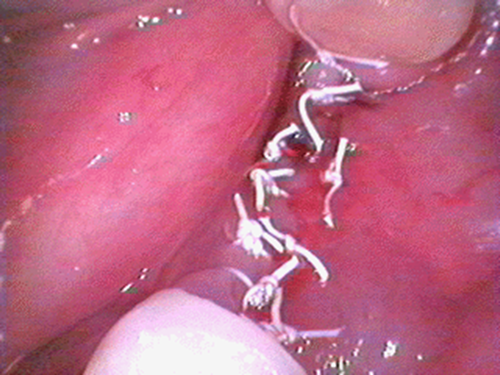

この患者様は、右上の奥歯の歯茎から出血してくるとのことで来院されました。歯周組織検査とレントゲンで診断を行った結果、重度の歯槽膿漏が認められ、保存不可能の為、抜歯になると伝えたところ、入れ歯は絶対に嫌だと言われたので、インプラント治療となりました。CT撮影を行ったところ、上顎洞底までの距離が3ミリ程度しかなかったのですが、骨が固く、フィクスチャーの一次固定が良好だったので、開窓法による上顎洞底挙上術とフィクスチャーの埋入を同時に行いました。約10カ月後に二次手術を行い、上部構造をセットしました。また、右下の臼歯部のブリッジにも大きな二次カリエスが認められ、7番の遠心根が抜歯になり、6番、7番にインプラント治療をしました。